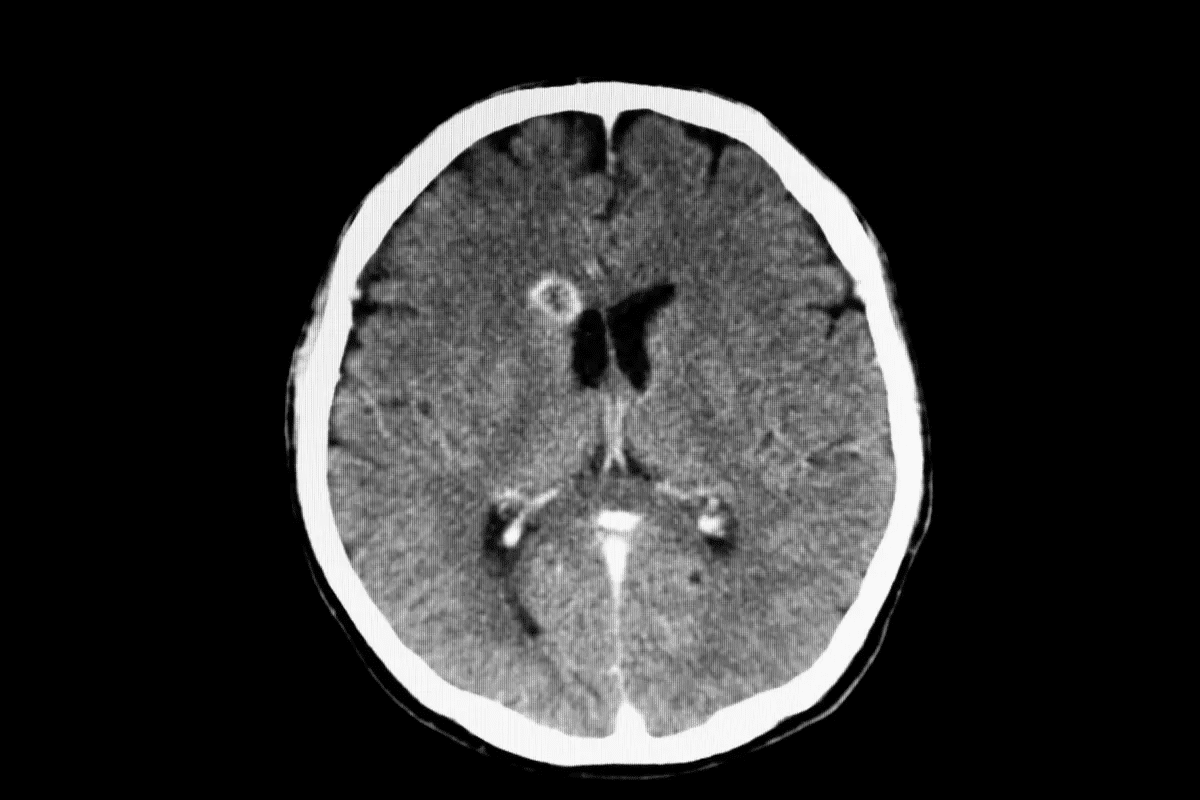

Brain Atrophy: The Visible Signs of Alzheimer’s

Alzheimer’s disease causes the brain to shrink significantly. This shrinkage affects nearly all brain functions. People with advanced Alzheimer’s can’t communicate well, recognize family, or take care of themselves.

Patterns of Brain Shrinkage

Brain shrinkage in Alzheimer’s is not even. Some areas, like the hippocampus, are hit hard first. This area is key for memory. As the disease gets worse, other parts like the temporal and parietal lobes shrink too. This leads to many cognitive and functional problems.

Ventricle Enlargement

Another sign of Alzheimer’s is bigger ventricles. The ventricles are spaces in the brain filled with fluid. When brain tissue shrinks, the ventricles get bigger. This is a key marker of the disease’s progress in scans.

Correlation Between Atrophy and Cognitive Decline

Brain shrinkage and cognitive decline are closely linked in Alzheimer’s. Studies show that as the brain gets smaller, thinking skills worsen. This link highlights the need to watch brain atrophy in managing and studying Alzheimer’s. It helps us understand how the disease progresses.

Visualizing the Alzheimer’s Brain: Diagnostic Imaging

Diagnostic imaging has changed how we diagnose and track Alzheimer’s disease. It helps us see the brain’s changes as the disease progresses. We’ll look at MRI, PET scans, and new technologies for viewing the Alzheimer’s brain.

Detecting Structural Changes with MRI

Magnetic Resonance Imaging (MRI) is key for spotting brain changes in Alzheimer’s. It shows the brain’s details, helping find atrophy in certain areas. This info is vital for diagnosing and tracking the disease.

One big plus of MRI is measuring brain structure volumes. For example, it can show hippocampal atrophy, a sign of Alzheimer’s. Here’s a table showing brain volume differences between healthy people and those with Alzheimer’s: